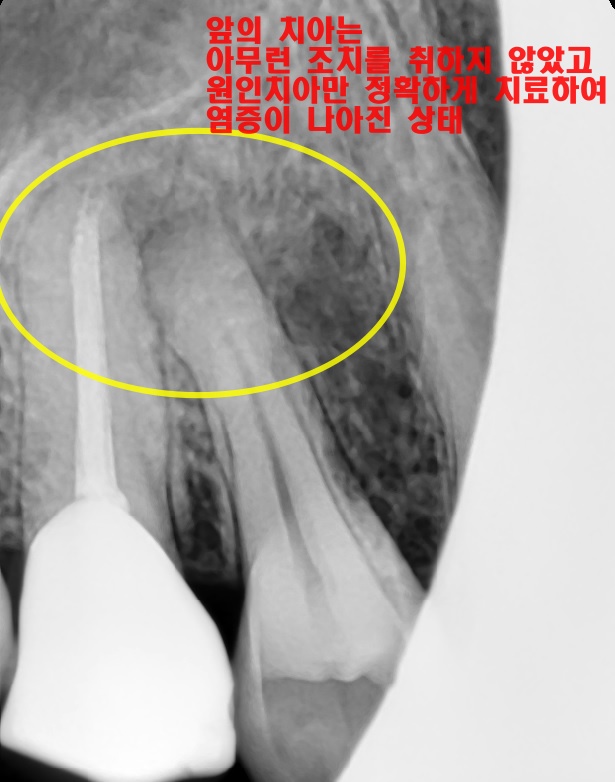

4. 엑스레이만 믿었다면 과잉진료로 이어졌을 사례

– 장비: 치근단 엑스레이, 기법: 활력 검사

​염증 소견이 두 개 치아에 걸쳐서 보였던 환자 사례입니다. 표면적으로 보면 두 치아 모두 신경치료가 필요해 보였습니다.​

하지만 치수 생활력 검사(치아의 신경이 살아있는지 확인하는 검사)를 통해서 제1소구치는 손상이 되지 않았고 염증의 원인은 제2소구치임을 명확히 밝혀내었습니다.

치근단병소

​제2소구치만 신경치료 후 씌우는 치료를 진행하였고요. 제1소구치에는 아무런 처치를 하지 않았음에도 치아 뿌리 쪽 염증이 모두 해소되는 것을 확인할 수 있었습니다.​

치수 생활력 검사를 시행하지 않은 채, 엑스레이에만 의존하여 판단했더라면, 불필요한 치아마저 치료를 하게 되는 최악의 상황을 맞이했을 것 같네요.